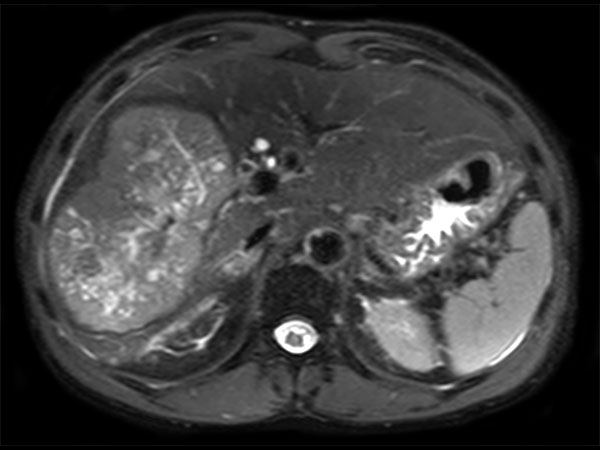

Axial T2w SPAIR

Axial T2w SPAIR SENSE = 2 in AP direction

Axial T2w SPAIR SENSE = 4 in RL direction